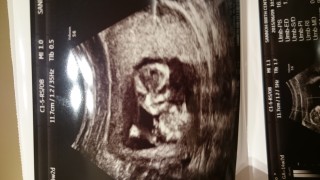

写真:14w2d:ちひろんさん

CRL85.2mm推定66g

とてもよく動く子で順調に成長しているとのこと!食べづわりと連日続いた偏頭痛もようやく治りました。